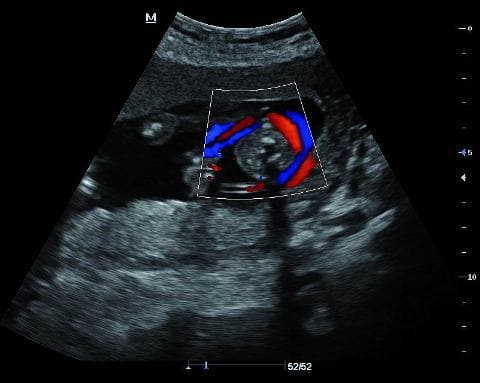

1) УЗИ исследование органов брюшной полости, КТ, Rо-графия легких с целью обнаружения одиночных или многокамерных кист. При обнаружении кист пункционное их исследование недопустимо во избежание фатального исхода для пациентов.

Эхинококкоз печени на УЗИ